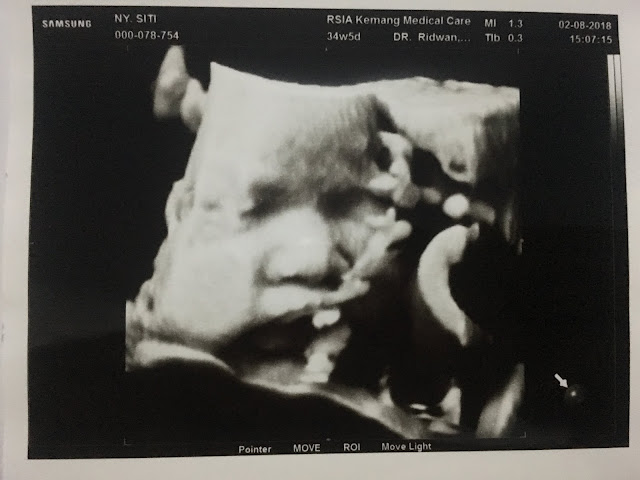

Menurutku dr Ridwan dan dr Agung so so ya… Bedanya cuma, dr Ridwan sangat pro Gentle Birth sedangkan dr Agung ini sangat pro dari sisi akademis (based on journal, WHO, etc). Dikasih bonus USG 4D dari dokter Ridwan (kalo bayar 675rb hehe), seneng banget si dedek sehat dan bebas dari lilitan tali pusat. Oh iya, di dokter Ridwan usia kandungan aku di-adjust lagi karena ternyata selama ini aku salah dong, aku kira usia kehamilan dimulai dari Hari Terakhir Haid Terakhir eh ternyata Hari Pertama Haid Terakhir. Alhamdulillah it means BB dedek nggak kebesaran.

Mirip siapa yaaaaah? Pipinya kayaknya aku banget!